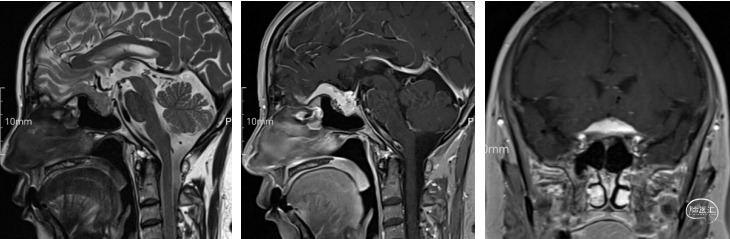

头颅增强核磁:蝶鞍可见片条状异常信号影并向前延伸,长度约33mm,高约14mm,垂体显示不清,视交叉受压,增强后强化明显,局部欠均匀,可见脑膜尾征,考虑为脑膜瘤可能。

术后核磁:肿瘤切除干净,垂体及垂体柄保留完好,术区无出血。